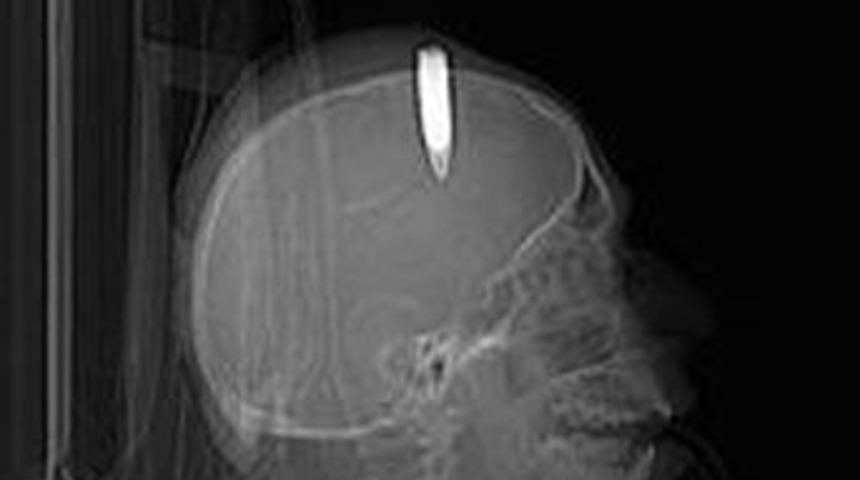

Evine giren hırsızın peşine düşen, hırsızın ateş etmesi sonucu kafasının ön kısmına isabet eden mermiyle yaralanan 60 yaşındaki Bayram Karakoyunlu, 34 yıldır kafasındaki tabanca mermisiyle yaşıyor. Karakoyunlu ilçesinde yaşayan Karakoyunlu, 1977'de evinde otururken dışardan ses geldiğini, evin kapısını açınca hırsızla karşılaştığını belirterek, ''Bahçe kapısını açınca hırsızın alnıma yakın yerden tabancasını ateşlediğini gördüm, düşmüşüm, gerisini hatırlamıyorum'' dedi.

Doktorların o dönemde mermiyi çıkarmakta sakınca gördükleri için müdahale etmediklerini, çıkardıkları takdirde ölebileceğini belirten Karakoyunlu, ''34 yıldır kafamda mermiyle yaşıyorum. Bazı sıkıntılarım dışında bir şikayetim yok. Tek endişem aniden felç olmam, ondan korkuyorum. Olaydan sonra hırsız da kayboldu gitti. Kim olduğunu bile öğrenemedim'' diye konuştu.

Iğdır Devlet Hastanesi Başhekim Yardımcısı Dr. Turgut Anuk, bu türden bir vakada kişinin yaşamasının mucize olduğunu, kafadaki merminin bazı sıkıntılar çıkarabileceğini, bunun normal olduğunu belirtti. Dr. Anuk, 34 yıl bu şekilde mermiyle yaşamanın ender bir durum olduğunu ifade ederek, ''Kurşun alından girmiş, ilerleyerek arka kısmına gelmiş. Merminin 34 yıldır kafasında durması hastada baş ağrısı yapıyor. Merminin yerinden oynatılması durumunda hastanın sağlığı daha çok tehlikeye girer. O zaman doktorlar 'ölüm riski var' diye ameliyatla mermiyi çıkarmamışlar'' dedi